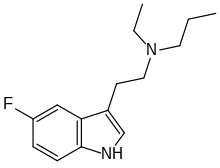

| 5-Fluoro-DMT | artificial | 5-F | CH3 | CH3 | 5-fluoro-N,N-dimethyltryptamine | 22120-36-1 |

| 5-Fluoro-MET | artificial | 5-F | CH3 | CH2CH3 | 5-fluoro-N-methyl-N-ethyltryptamine | |

| 5-Fluoro-DET | artificial | 5-F | CH2CH3 | CH2CH3 | 5-fluoro-N,N-diethyltryptamine | |

| 5-Fluoro-EPT | artificial | 5-F | CH2CH3 | CH2CH2CH3 | 5-fluoro-N-ethyl-N-propyltryptamine | |

| 5-Fluoro-DPT | artificial | 5-F | CH2CH2CH3 | CH2CH2CH3 | 5-fluoro-N,N-dipropyltryptamine | |

| 5-Fluoro-PiPT | artificial | 5-F | CH2CH2CH3 | CH(CH3)2 | 5-fluoro-N-propyl-N-isopropyltryptamine | |

| 5-Fluoro-PcBT | artificial | 5-F | CH2CH2CH3 | CH(CH2)3 | 5-fluoro-N-propyl-N-cyclobutyltryptamine | |

| 5-Fluoro-iPcBT | artificial | 5-F | CH(CH3)2 | CH(CH2)3 | 5-fluoro-N-isopropyl-N-cyclobutyltryptamine | |

| 5-Fluoro-DiPT | artificial | 5-F | CH(CH3)2 | CH(CH3)2 | 5-fluoro-N,N-diisoproptryptamine | |

| 5-Fluoro-sBALT | artificial | 5-F | CH(CH3)CH2CH3 | CH2CH=CH2 | 5-fluoro-N-sec-butyl-N-allyltryptamine | |

| 5-Fluoro-M1MALT | artificial | 5-F | CH3 | CH(CH3)CH=CH2 | 5-fluoro-N-methyl-N-(1-methylallyl)tryptamine | |